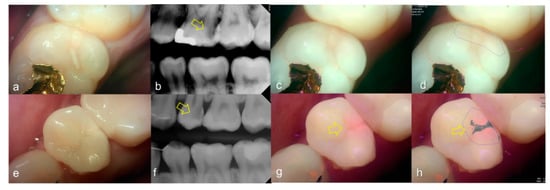

Representative images of QLF and bitewing radiograph of occlusal dental caries are shown in Figure 4 and Figure 5.

Figure 4.

Occlusal dental caries: (a–d) QLF caries score 1 (fluorescence loss and red fluorescence present as a line or spot in pits and/or fissures) and radiographic caries score 0 (no radiolucency visible) on #36; (e–h) QLF caries score 2 (fluorescence loss and red fluorescence glow extending around pits and fissures) and radiographic caries score 0 (no radiolucency visible) on #36; (i–l) QLF caries score 3 (red fluorescence glow extending around pits and fissures and a dark shadow from dentin present) and radiographic caries score 0 (no radiolucency visible) on #37; (a,e,i): white-light image of QLF; (b,f,j): fluorescence image of QLF; (c,g,k): bitewing radiograph; (d,h,l): analyzed QLF image using QA2 software.